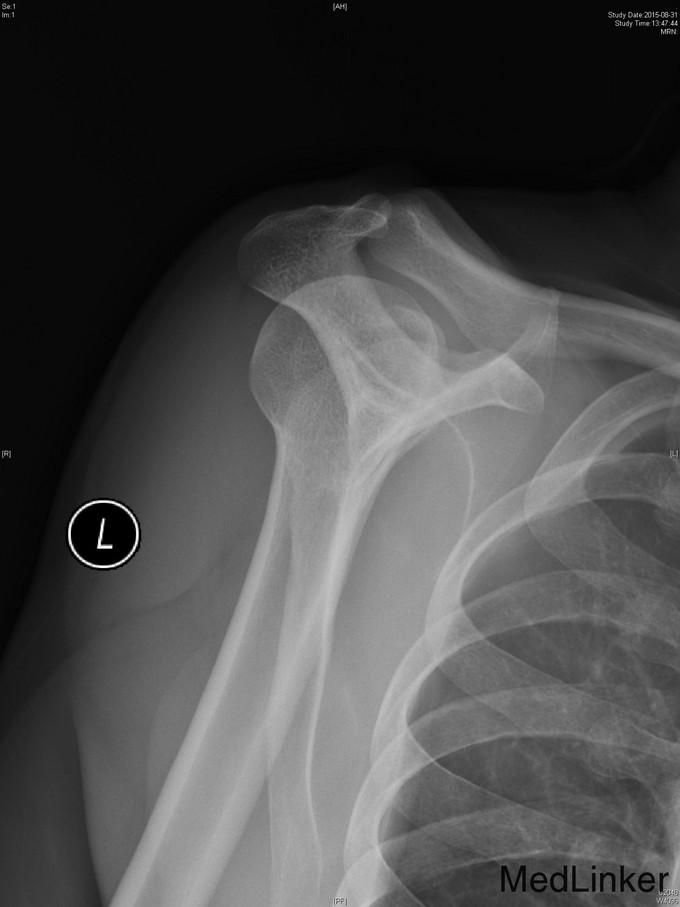

主诉:左肩扭伤后疼痛不适伴弹响10余年,加重3月。 现病史:患者10余年前扭伤左肩关节后出现疼痛不适等症状,伴活动时弹响,以运动时明显。患者当时未重视,未就诊。10余年来患者左肩疼痛不适症状反复发作,曾至外院行局部理疗、小针刀等保守治疗,效果不佳。3月前患者再次扭伤左肩,当即感觉左肩症状加重。来我院就诊,我院行MRI检查示:左肩盂唇信号异常及肱二头肌长头肌腱信号异常。

右上肢、双下肢肌力及活动度正常。左肩关节周围肌肉萎缩,左肩前方压痛(+),无明显肿胀。左肩关节活动度尚正常,Hawking征(-),Neer征(+-),Jobes征(+-),Speed(+),O’Brein征(+),Drop Arm(-)、熊抱试验(-)。Apprehension征(+),ADT(+),外展肌力(Ⅴ)级。双上肢感觉正常。

1、诊断:左肩创伤性前不稳定,左肩SLAP损伤。 2、治疗:全麻下行左肩关节镜下前盂唇、上盂唇修补术。